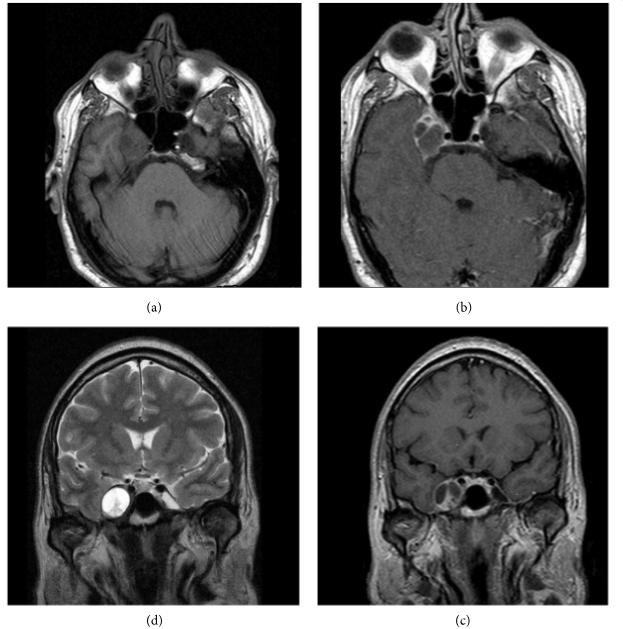

三叉神经鞘瘤是比较常见的非前庭神经鞘瘤,占颅内神经鞘瘤的1 ~ 8%,占颅内肿瘤的0.1 ~ 0.5%。常常发生在中年人身上,也可以发生在任何年龄,包括儿童。三叉神经鞘瘤可以发生在三叉神经根和远端颅外支之间的任何地方。它们的临床表现取决于肿瘤的位置和大小。比较常见的症状包括面部感觉减退、头痛、头晕和共济失调。

1、详细的术前的影像学评估,包括对三叉神经根、三叉神经的Meckel's腔、海绵窦,对于这些重要结构识别清楚,看看肿瘤具体侵犯的位置以便遗漏。